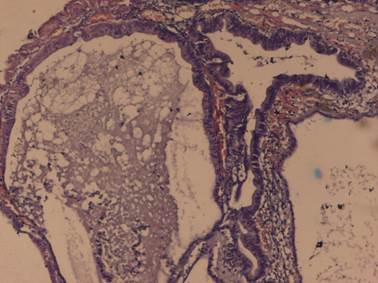

The operated specimen was encapsulated, solid and cystic with visible areas of capsular breach, of size 21 × 18 × 7 cm, and encased the upper pole and the middle region of the kidney. Perirenal fat and Gerota’s fascia were not involved. Microscopically, the tumour consisted of elongated, anastomosing tubules separated by lakes of mucin from a prominent spindle cell area. The tubules were composed of low cuboidal cells with amphophilic to eosinophilic cytoplasm with mild anisonucleosis. Foci of SD comprising about 30% of the tumour were seen, with pleomorphic low-grade nuclei. No lymphovascular invasion was noted (Figures 1 and 2). Alcian blue stain showed the typical blue-coloured mucin in the stroma between the tubules and the cords (Figure 3). The tumour cells were diffusely positive for cytokeratin 7 (Figure 4), EMA and vimentin but negative for CD10. Six cycles of adjuvant chemotherapy (vincristine, Adriamycin and cyclophosphamide [VAC] regimen), comprising cisplatin 50 mg/m2, vincristine 1.0 mg/m2, Adriamycin 40 mg/m2/day (Dako, Germany), cyclophosphamide 1000 mg/m2 and actinomycin-D 0.5 mg/m2 followed by 50 Gy/25 fractions of cobalt-60 teletherapy were given. The patient tolerated the therapy well without any appreciable adverse effects and unremarkable blood chemistry findings. Follow-up after 12 months demonstrated that the patient was doing well with no evidence of recurrence or metastasis.

Figure 1. Microscopically, the tumour consisted of elongated, anastomosing tubules separated by lakes of mucin from a prominent spindle cell area. The tubules were composed of low cuboidal cells with an amphophilic to eosinophilic cytoplasm with low-grade nuclei. Foci of sarcomatoid differentiation were seen with pleomorphic high-grade nuclei without any evidence of vascular invasion. Haematoxylin and eosin, 10×.